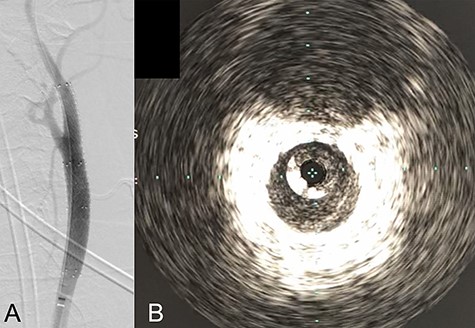

We performed CAS and started dual antiplatelet therapy 27 days after stroke onset to prevent further dissection and cerebral infarction recurrence. The dissection started 1.5-cm below the carotid bifurcation (Fig. 3A). An 8 fr guiding catheter (FlowGate2 Balloon Guide Catheter, Stryker, Fremont, CA, USA) was positioned at the proximal portion of the left CCA with a micro-guidewire (ASAHI CHIKAI Black, Asahi-Intecc, Nagoya, Aichi, Japan) crossing the dissected lesion. A distal protection device (SpiderFx Embolic Protection Device, Medtronic, Minneapolis, MN, USA) was deployed at the petrous portion of the ICA. IVUS was first advanced into the petrous ICA, and vessel wall imaging was performed by slowly withdrawing the device. IVUS imaging confirmed the existence of the dissection’s pseudo-lumen starting 1-cm proximal to the carotid bifurcation (Fig. 3C). IVUS provided the ICA and CCA diameters, which helped decide the most suitable stent (Fig. 3B and C). To adequately cover the dissection lesion, we placed two opened cell stents (Protégé, Medtronic, Minneapolis, MN, USA); one was an 8–6-mm tapered model with a length of 40 mm to cover the lesion from the distal CCA end to the proximal portion of ICA. Another was a 10-mm straight model with a length of 40 mm covering the CCA. Post-dilation was performed SterlingTM Balloon Dilation Catheter (Boston Scientific, Natick, MA, USA) with 5 × 20 mm covering both stents’ edges. The final angiography showed successful treatment with a smooth intra-arterial lumen (Fig. 4A). IVUS imaging showed sufficient stent coverage of the entire dissection lesion. It also confirmed a good expansion of the stent to the dissection area’s arterial wall with no plaque protruding the stents (Fig. 4B).

Angiography revealed the dissection starting proximal to the carotid bifurcation (Black arrow: A). IVUS provided the diameters of the ICA and CCA (B and D, respectively). IVUS imaging confirmed the pseudo-lumen of the dissection starting 1-cm proximal to carotid bifurcation (C) and the entry point of the dissection as well (Black arrow: C).

We would further like to note the usefulness of IVUS in this particular case. IVUS clearly visualized both the dissection’s entry point and the blood flow from true- to pseudo-lumen, the information of which is essential for treatment strategy planning. IVUS also provided helpful information to assess the stent’s coverage (Fig. 3). IVUS allowed us to predict the entire length of the arterial dissection before stent deployment [11]. Furthermore, IVUS provided important information for stent-size selection. Although the pseudo-lumen caused by the dissection made it difficult for us to precisely measure the true lumen diameter, IVUS allowed us to measure the diameter of the true lumen of the dissected artery, and we were able to select the appropriate stent for treatment. It also provided helpful information that proper stent apposition was established even after the stent deployment and post-balloon dilation, which indicated no additional angioplasty was necessary.